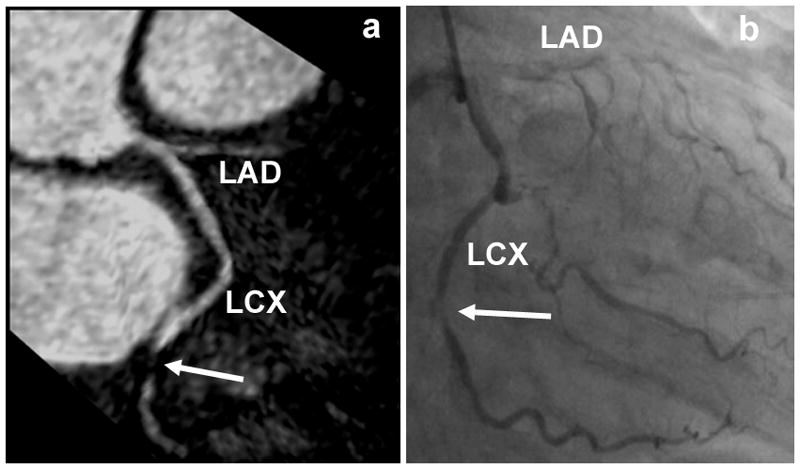

Figures 7a and 7b show reformatted coronary artery images from a 39 year old male patient acquired with the radial EPI technique. Long segments of the LM, LAD, and LCX are well depicted. No significant stenosis was found in this case and the coronary MRA images correlate well with the x-ray angiography image (Fig. 7c). Figure 8 shows coronary artery images from a 74 year old female patient illustrating the detection of significant stenoses in the distal LCX (shown as white arrow) and total occlusion of the LAD. Once again there is excellent correlation between the radial EPI coronary MRA technique (8a) and x-ray angiography (8b).

Figure 8.

Coronary artery images from a 74 year old female patient illustrating the detection of significant stenoses in the distal LCX (shown as white arrow) and total occlusion of the LAD. There is excellent correlation between the radial EPI coronary MRA (8a) and x-ray angiography (8b) images.